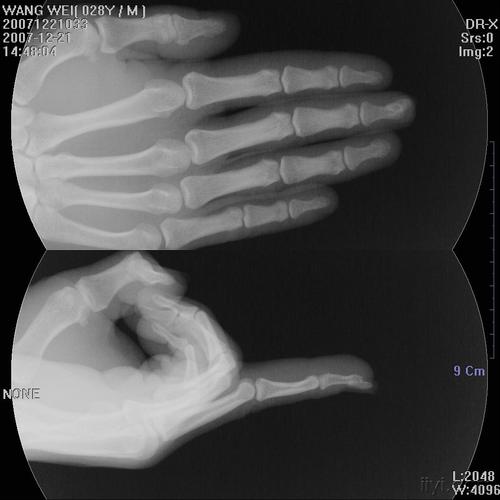

x光照片手,x光照片

患者的x光片.图片由杭州市中医院提供

手指x光片

求v字手的x光片或这张图原图

要一张左右手手掌骨骼图,x光的要,ct的图